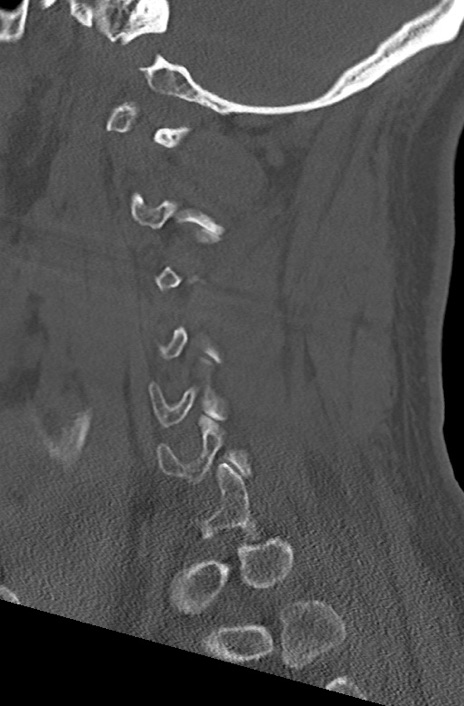

頚椎CT

矢状断像と横断像